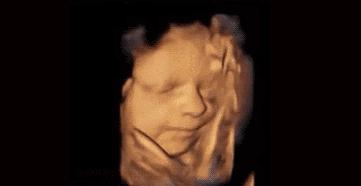

菌菌告诉你,小家伙不仅会做各种动作,表情更是丰富的不得了。

小脑袋一晃一晃的,我不答应,我不高兴,我要吃肉肉……

咦,妈妈在外面跟我说话,嘟嘴卖个萌先。

哈哈,妈妈肯定是被我萌到了,我都听到她的笑声了。

我还会吐舌头、扮鬼脸!